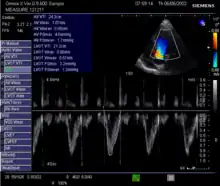

Echocardiography is a non-invasive method of quantifying cardiac output using ultrasound. Two-dimensional (2D) ultrasound and Doppler measurements are used together to calculate cardiac output. 2D measurement of the diameter (d) of the aortic annulus allows calculation of the flow cross-sectional area (CSA), which is then multiplied by the VTI of the Doppler flow profile across the aortic valve to determine the flow volume per beat (stroke volume, SV). The result is then multiplied by the heart rate (HR) to obtain cardiac output. Although used in clinical medicine, it has a wide test-retest variability.[8] It is said to require extensive training and skill, but the exact steps needed to achieve clinically adequate precision have never been disclosed. 2D measurement of the aortic valve diameter is one source of noise; others are beat-to-beat variation in stroke volume and subtle differences in probe position. An alternative that is not necessarily more reproducible is the measurement of the pulmonary valve to calculate right-sided CO. Although it is in wide general use, the technique is time-consuming and is limited by the reproducibility of its component elements. In the manner used in clinical practice, precision of SV and CO is of the order of ±20%.